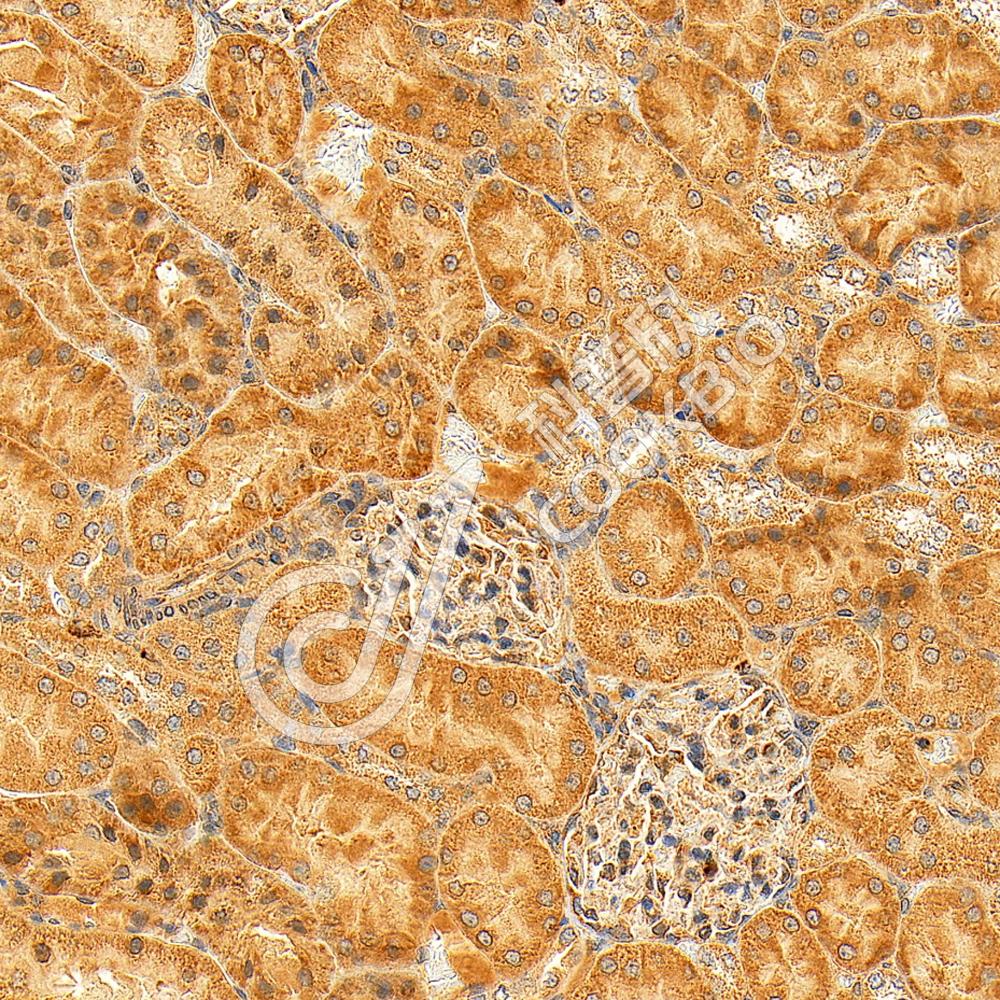

IHC检测DNAJC19蛋白(货号 K1344994).

样品: 小鼠肾, 4%多聚甲醛 (货号KSG1101) 固定12-24小时.

抗原修复: Tris-EDTA抗原修复液(pH 9.0) (KSG1203), 98℃, 20分钟.

—抗: 1: 1600稀释, 4℃ 孵育过夜.

二抗: S-vision免疫组化多聚二抗(山羊抗兔),即用型 (货号KB3906), 室温孵育20分钟.

样品: 大鼠肾, 4%多聚甲醛 (货号KSG1101) 固定12-24小时.